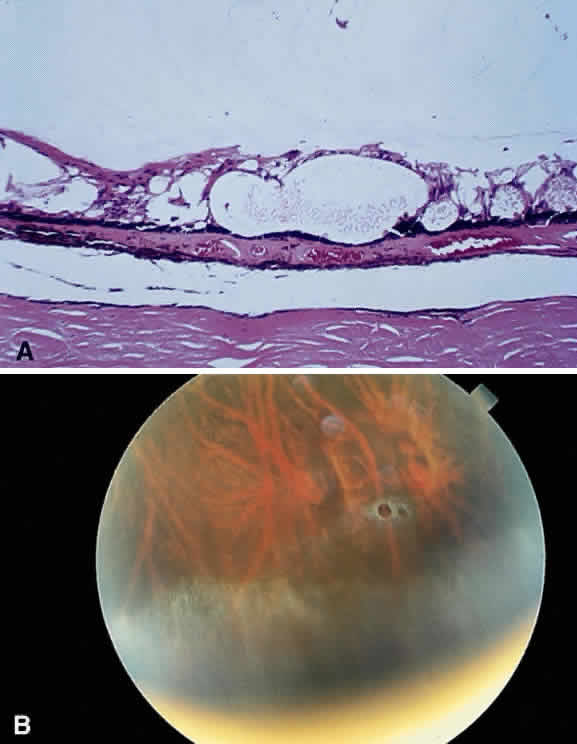

Fibrous tissue may originate from the choroid and proliferate through breaks

in Bruch's membrane into the subpigment epithelial or subretinal

spaces,4 hence the white appearance of disciform macular degeneration (Fig. 16). Fibrous tissue also may originate from fibroblasts located in the adventitia

of retinal vessels and may contribute to the white appearance

of vascularized membranes (Fig. 17A), such as those seen in proliferative diabetic retinopathy (see Fig. 17B) or arterioles after vascular occlusion (see Fig. 6). The accretion of collagen in the wall of the vessel in arteriolosclerosis

Fig. 17. A. A histologic section stained with H & E demonstrating vascularized

membranes on the disc and retina. Tractional retinal detachment is present. Notice

the subretinal fluid (amorphous eosinophilic material). B. Fundus photograph of fibrous tissue emanating from the disc in patient

with proliferative diabetic retinopathy. The disc is pale; the macula

is edematous with exudate. Pigmented laser spots are visible temporally. Fig. 17. A. A histologic section stained with H & E demonstrating vascularized

membranes on the disc and retina. Tractional retinal detachment is present. Notice

the subretinal fluid (amorphous eosinophilic material). B. Fundus photograph of fibrous tissue emanating from the disc in patient

with proliferative diabetic retinopathy. The disc is pale; the macula

is edematous with exudate. Pigmented laser spots are visible temporally.